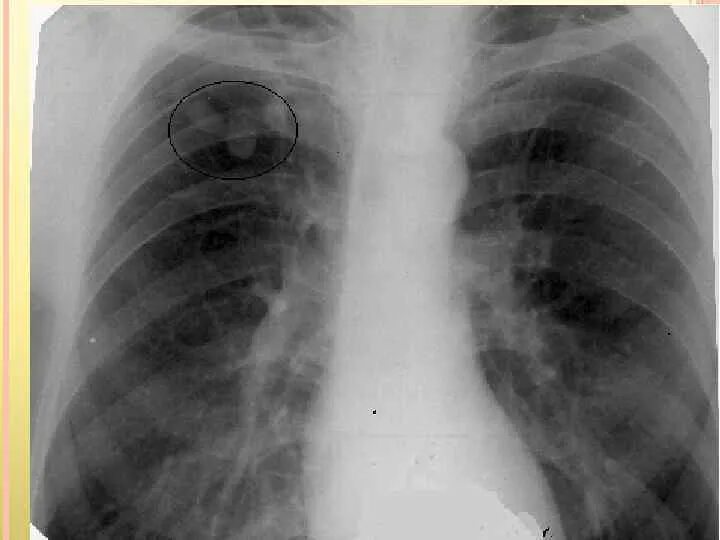

Аортокоронаросклероз легких что это такое